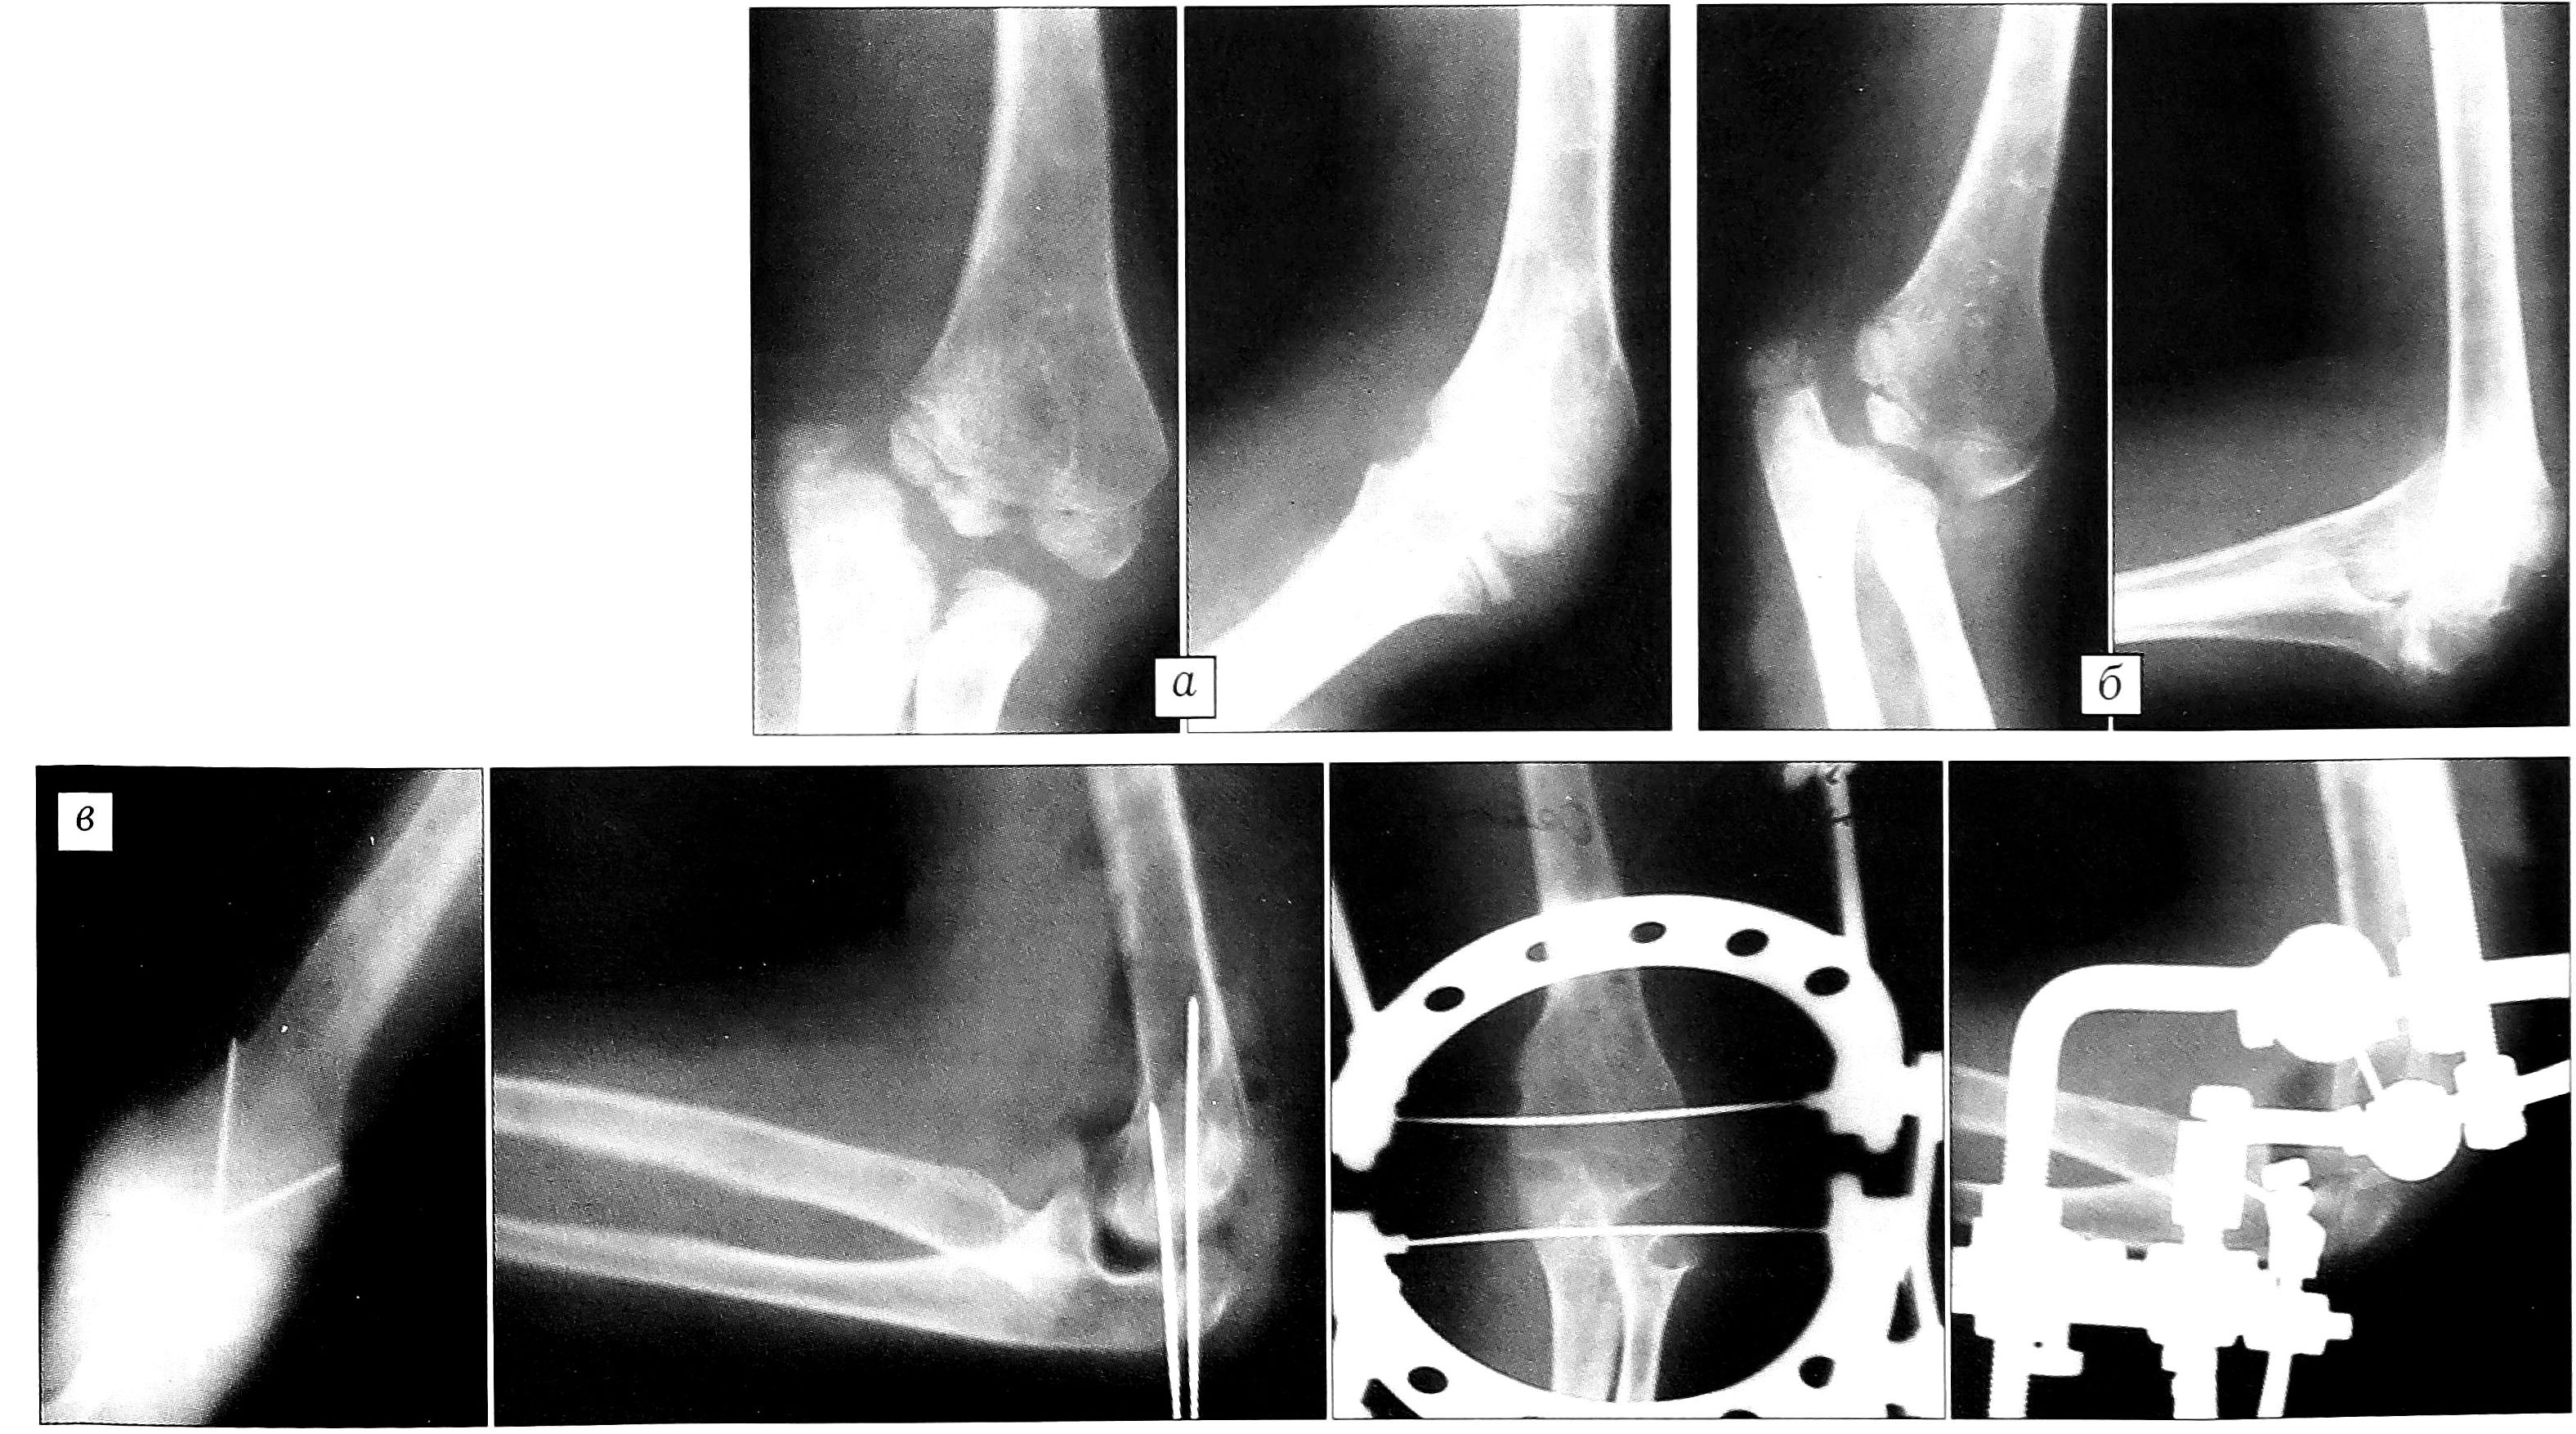

Неудовлетворительный результат отмечен нами в одном случае (1,8%). Больному О. с приводящей внутреннеротационной контрактурой плечевого сустава вследствие родового повреждения плечевого сплетения в возрасте 6 лет были выполнены деротационная остеотомия плечевой кости в нижней трети и остеосинтез металлической пластиной. Через 4 года после операции сформировалась варусная деформация локтевого сустава, наступил подвывих (рис. 5, а), а через 6 лет — медиальный вывих костей предплечья (рис. 5, б). Для коррекции данной деформации потребовалось этапное оперативное лечение — открытое устранение вывиха костей предплечья, моделирующая артропластика, разработка движений в аппарате Волкова—Оганесяна и длительное реабилитационное лечение (рис. 5, в).

Рис. 5. Больной О. Диагноз: последствия натального повреждения левого плечевого сплетения, приводящая внутреннеротационная контрактура левого плечевого сустава. а — рентгенограммы через 4 года, б — через 6 лет после деротационной остеотомии плечевой кости, выполненной в возрасте 6 лет: подвывих и вывих костей левого предплечья; в — на этапах оперативной коррекции в возрасте 12 лет.